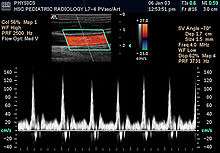

- Pulsed wave (PW) Doppler: Doppler information is sampled from only a small sample volume (defined in 2D image), and presented on a timeline

- Duplex: a common name for the simultaneous presentation of 2D and (usually) PW Doppler information. (Using modern ultrasound machines, color Doppler is almost always also used; hence the alternative name Triplex.)

Sonography can be enhanced with Doppler measurements, which employ the Doppler effect to assess whether structures (usually blood)[16] are moving towards or away from the probe, and its relative velocity. By calculating the frequency shift of a particular sample volume, for example flow in an artery or a jet of blood flow over a heart valve, its speed and direction can be determined and visualised. This is particularly useful in cardiovascular studies (sonography of the vascular system and heart) and essential in many areas such as determining reverse blood flow in the liver vasculature in portal hypertension. The Doppler information is displayed graphically using spectral Doppler, or as an image using color Doppler (directional Doppler) or power Doppler (non directional Doppler). This Doppler shift falls in the audible range and is often presented audibly using stereo speakers: this produces a very distinctive, although synthetic, pulsating sound.

All modern ultrasound scanners use pulsed Doppler to measure velocity. Pulsed wave machines transmit and receive series of pulses. The frequency shift of each pulse is ignored, however the relative phase changes of the pulses are used to obtain the frequency shift (since frequency is the rate of change of phase). The major advantages of pulsed Doppler over continuous wave is that distance information is obtained (the time between the transmitted and received pulses can be converted into a distance with knowledge of the speed of sound) and gain correction is applied. The disadvantage of pulsed Doppler is that the measurements can suffer from aliasing. The terminology "Doppler ultrasound" or "Doppler sonography", has been accepted to apply to both pulsed and continuous Doppler systems despite the different mechanisms by which the velocity is measured.